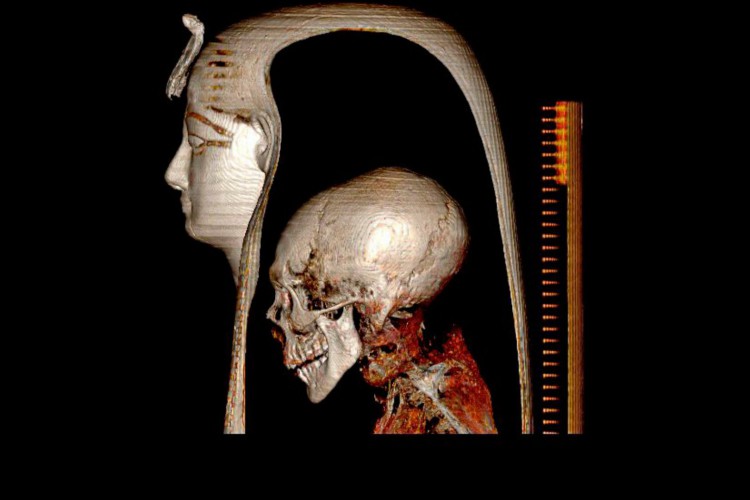

Pesquisadores egípcios conseguiram descobrir os segredos de uma múmia real sem remover suas bandagens, graças a imagens médicas que revelaram novas técnicas de embalsamamento lançadas na época de Amenófis I, também conhecido como Amenotepe I, mais de 1.500 anos antes de Cristo.

Este faraó filho de Ahmose Nefertari e de Ahmose I, fundador da XVIII dinastia (-1550 a -1292 a.C.), foi o primeiro a ser mumificado com os braços cruzados. Também foi o último, cujo cérebro não foi retirado do crânio no momento de sua mumificação, relata um comunicado do Ministério egípcio de Turismo e Antiguidades nesta terça-feira, 28.

Esta múmia, descoberta em Luxor em 1881, é a única, cujas bandagens que envolvem estreitamente o corpo nunca foram desenvolvidas por arqueólogos, para preservar sua máscara funerária, assim como as coroas de flores em volta de sua cabeça.

Esta pesquisa foi realizada por Sahar Saleem, professora de radiologia da Universidade do Cairo, e Zahi Hawass, figura conhecida, e às vezes polêmica, da egiptologia. Juntos, submeteram a múmia a uma técnica de imagem médica em 3D muito avançada: a tomografia assistida por computador.